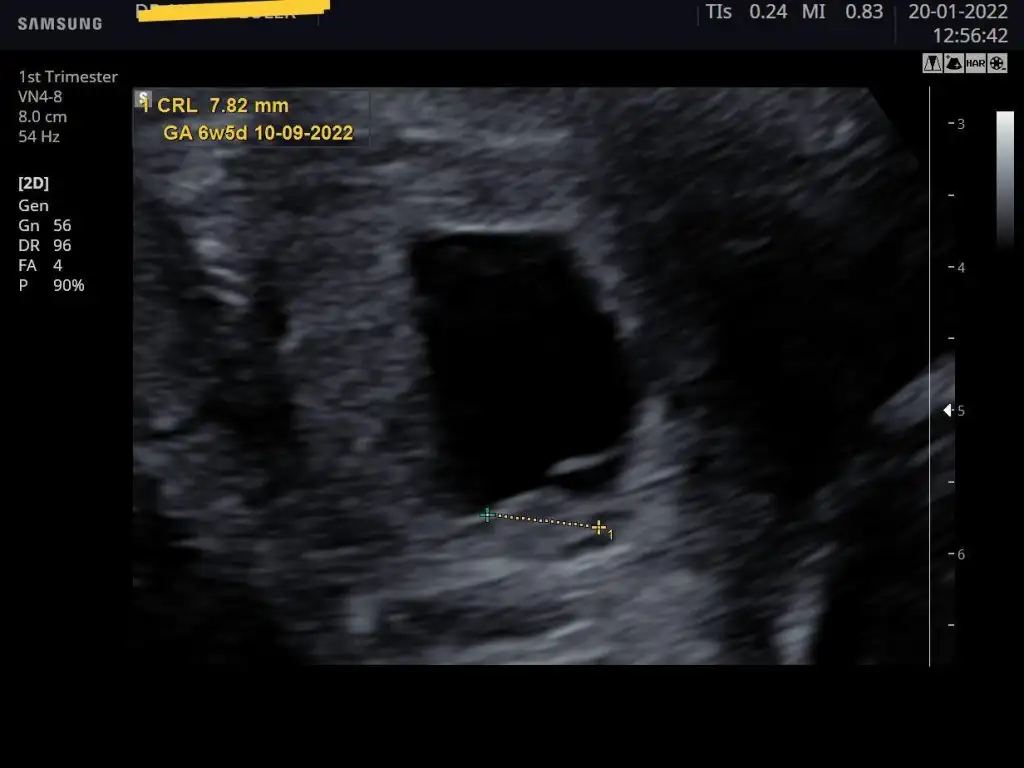

Sağ tarafımda daha çok batma hissediyordum, o da zaten oraya tutunmuş👶 Biraz şekilsiz ama bu da bizim ilk resmimiz🤍 Tahminler varsa alabiliriz🥰

Eklentiler

• IMG_20220120_152209.webp

IMG_20220120_152209.webp

22 KB · Görüntüleme: 91